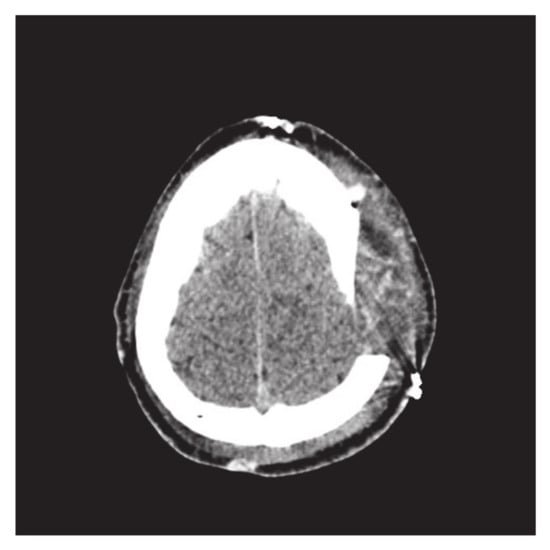

This subsection addresses the critical analysis of different schemes based on Bézier-like functions such as G C 2 , G C 1 , C 1 rational cubic Ball curves, NURBS curves and B-spline curve of degree three. Different types of fractures have been constructed using CT scan, such as in Figure 10. Initially, the C 1 rational cubic Ball curve is used to construct the boundary curve of the fractured part, as shown in Figure 11. This scheme works well for small fractures but it reduces the smoothness and flexibility when the defected part become bigger and irregular, as shown in Figure 12 and Figure 13. However, the results obtained by G C 1 , G C 2 rational cubic Ball curves are better, smoother and more flexible than the C 1 rational cubic Ball curve due to the presence of more shape parameters, as shown in Figure 14. The comparison of all curves is shown in Figure 15. In this figure, the red curve is obtained using the G C 1 rational Ball, the blue and green curves are obtained using the C 1 rational Ball.

To check the validity of G C 1 and G C 2 curves, they are applied to construct the comparatively bigger fractured part, as shown in Figure 16. The results of curve fitting using G C 1 , G C 2 curves show the rigidity of the curve resulting in limitation of these methods, as shown in Figure 17, Figure 18 and Figure 19. By dividing the fractured part into segments, the curve become smoother and flexible. The flexibility and smoothness is totally dependent on the number of segments of the fractured part. However, by increasing the number of segments, the required number of control points and and shape parameters are also increased, which is not easy to handle and increases the computational cost.

Figure 16. CT scan slice with big fractured part.